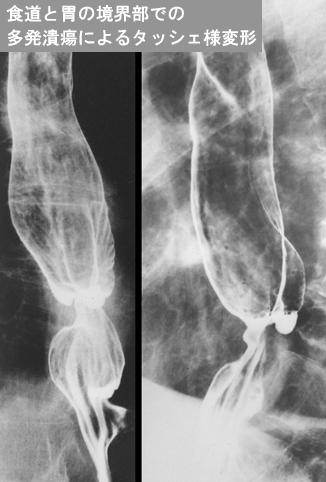

[Image-ID:12206]